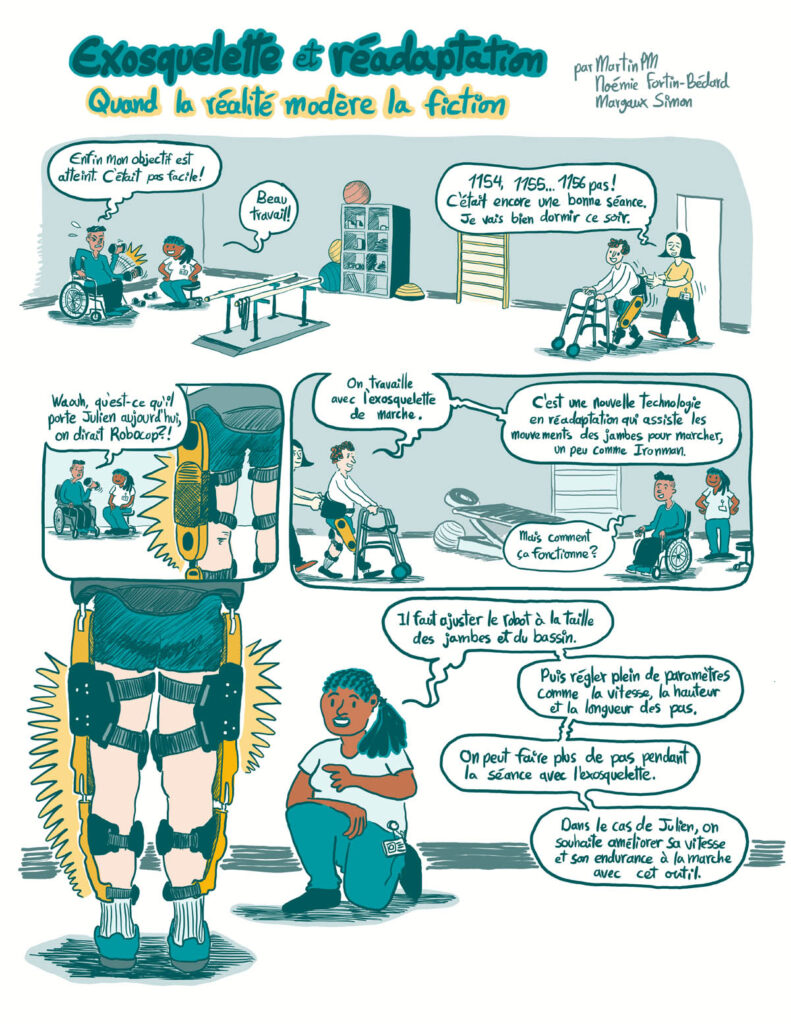

Une BD pour démystifier l’exosquelette de marche

Qu’est-ce que l’exosquelette de marche? Qui peut l’utiliser, et pourquoi?

Une BD pour démystifier l’exosquelette de marche

Chercheuses du Cirris

Autres membres de l'équipe de recherche

- Noémie Fortin-Bédard

- Margaux Simon

Collaborateur

- Martin Patenaude-Monette, bédéiste